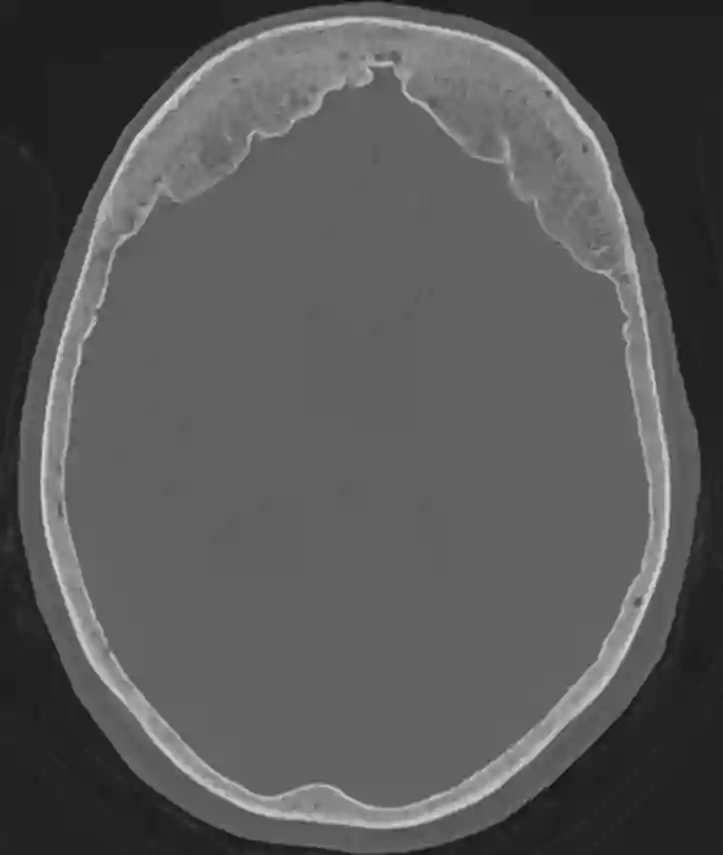

Bifrontale Hyperostose im CT

Axiales CT Bild im Knochenfenster eines Patienten mit einer bifrontalen Hyperostose.